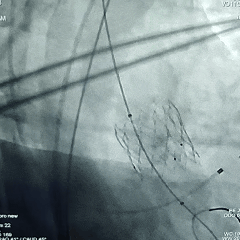

术中情况回顾

主动脉根部造影

18mm球囊预扩张

瓣膜初始定位

瓣膜展开至工作位

瓣膜工作位评估

瓣膜工作位多角度评估

瓣膜稳定脱钩

瓣膜脱钩后造影,瓣膜形态不佳决定后扩张

20mm球囊后扩张

瓣膜后扩后造影测压,无压差